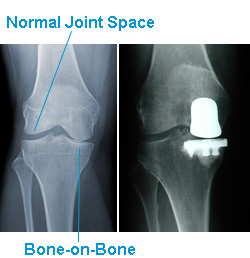

Without your cartilage protecting your knees, your bones grind against each other, which causes you pain: pain that you can feel climbing stairs, working in the garden, or just trying to sit down. It may even keep you up at night.

Osteoarthritis, the most common form of arthritis, is a wear and tear condition that destroys joint cartilage, and it typically develops after years of constant motion and pressure in the joints. As the cartilage continues to wear away, bone begins to rub against bone, causing the irritation, swelling, stiffness, and discomfort commonly associated with arthritis.

Total Knee Replacement

Your surgeon may recommend knee replacement surgery if you have significant arthritis. Surgeons don't actually replace the joint as is commonly thought. Your surgeon actually replaces the damaged cartilage found at the ends of the bones in your knee joint. Perhaps it should be called "cartilage replacement surgery."

Knee replacement implants to resurface the joint are typically made from metal alloy and polyethylene (plastic). The implants are designed to restore function and eliminate as much discomfort as possible while allowing you to return to a more active lifestyle.